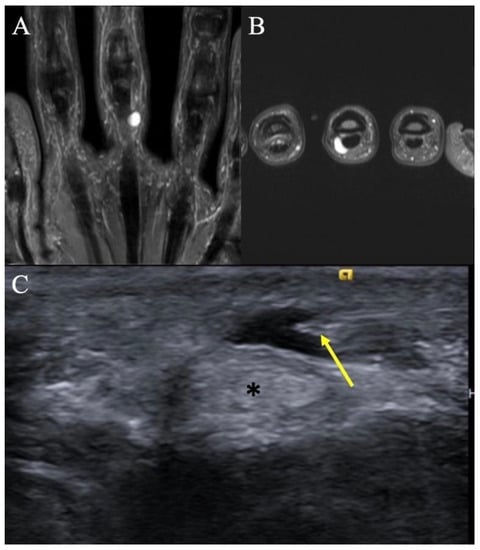

2.5. Glomus Tumors

2.5.2. Imaging Appearance